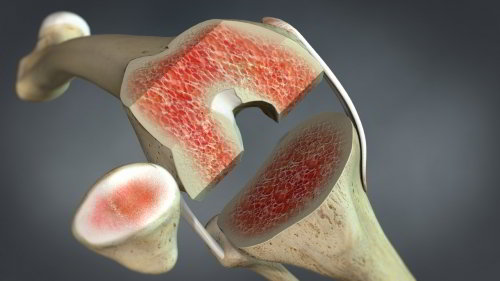

Osteolyse durch Kunststoffabrieb

Eine weitere Ursache für eine Lockerung der Knieprothese ist die aseptische Osteolyse (Knochenabbau). Diese Art der Lockerung beruht nicht auf einem bakteriellen Prozess. Stattdessen kommt es zu einem Abrieb von Polyethylenpartikeln aus dem Inlay der Knieprothese. Dieser Vorgang kann bei dafür empfänglichen Patienten eine Immunantwort im Gewebe provozieren. Die dadurch freigesetzten Fresszellen (Makrophagen) können den Plastikabrieb jedoch nicht eliminieren. Die Immunreaktion geht also nicht zurück. Es kann zu einer Osteolyse in der Umgebung der Knieprothese kommen. Dies zerstört die Verankerung der Knieprothese im Knochen und die Prothese löst sich.